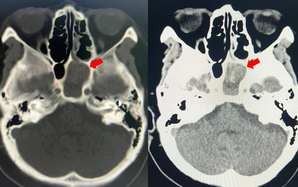

Lời cảnh báo từ trường hợp “cô gái trẻ vừa đưa tới bệnh viện thì hôn mê”

(NLĐO)-Những cơn đau đầu âm ỉ kéo dài hoặc tái diễn không rõ nguyên nhân là lời cảnh báo sớm của căn bệnh đột quỵ nguy hiểm chết người.